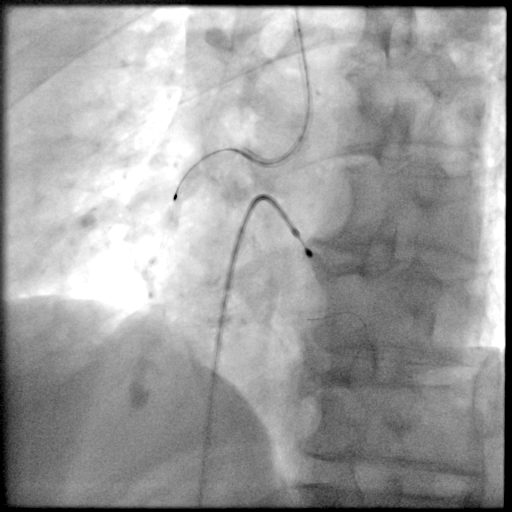

PCI过程-冠状动脉旋切(轨道旋磨)术-1

IVUS导管无法通过,微导管辅助下,将旋磨导丝置于RCA远端,应用1.0mm磨头以13万转反复旋磨钙化病变处(每次15秒,磨头推进速度不超过10 mm/s)

PCI过程-冠状动脉旋切(轨道旋磨)术-2

微导管辅助下,将旋磨导丝置于RCA远端,应用1.0mm磨头以13万转反复旋磨钙化病变处(每次15秒,磨头推进速度不超过10 mm/s)

PCI过程-冠状动脉旋切(轨道旋磨)术-3

共计旋切170秒,术后,狭窄较前减轻